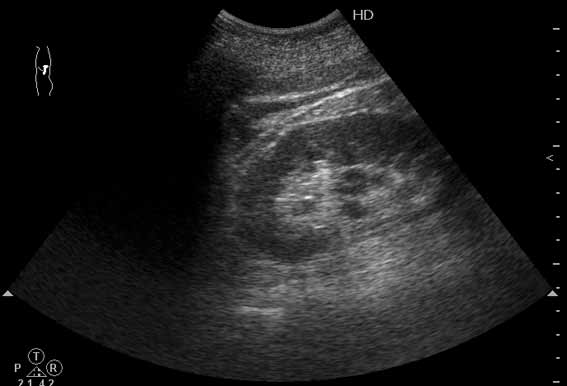

Изменения забрюшинного пр-ва при о.панкреатите (УЗИ)

Мужчина средних лет с болями в животе.

Сонограмма выполнена из левого поясничного доступа.

О каком заболевании нужно подумать в первую очередь по такой картинке?

Друзья, вы увлеклись изучением почки. Реально в почке ничего существенного нет. Еще раз просмотрите видео.

Наводящий вопрос: что это (стрелка)?